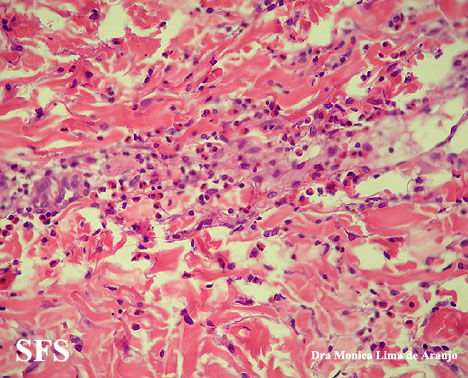

eosinophilic annular erythema